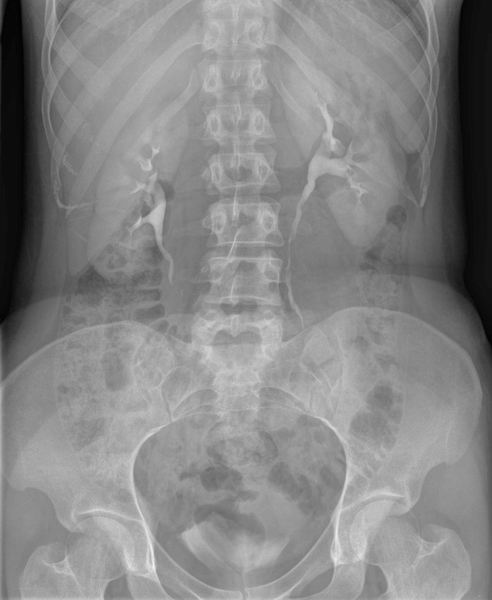

Bekken